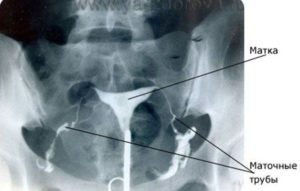

Снимок МСГ: маточные трубы с контрастом.

Нормальная проходимость позволяет получить достаточно четкое изображение для дальнейшего исследования полости матки и труб. В этом же случае незначительная часть контрастного вещества попадает в брюшную полость, растворяясь там. Остатки далее выходят в виде скудных выделений, не причиняя, как правило, особого дискомфорта женщине.

Метросальпингография позволяет узнать форму матки пациентки, состояние труб и их проходимость, а также имеются ли в рассматриваемой области спайки.